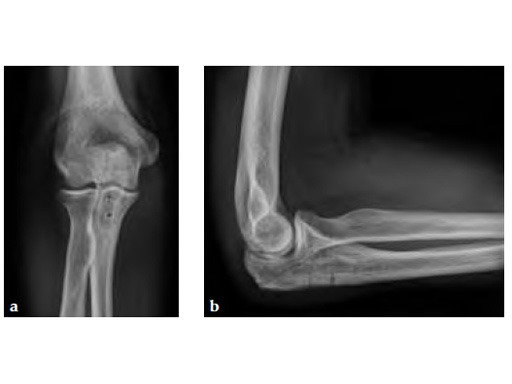

30-year-old male.

Fig 1ab Preoperative AP and lateral x-rays.